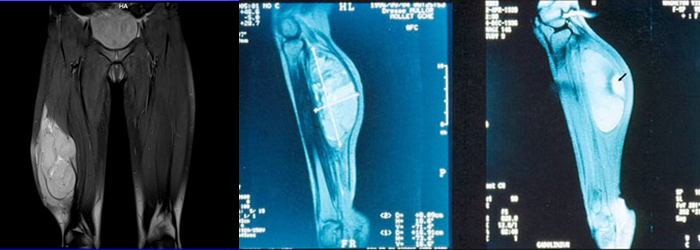

Soft tissue sarcomas are cancerous (malignant) tumors that originate in the soft tissues of your body. Soft tissues connect, support and surround other body structures. The soft tissues include muscle, fat, blood vessels, nerves, tendons and the lining of your joints (synovial tissues). A large variety of soft tissue sarcomas can occur in these areas.

• Soft tissue sarcomas can occur anywhere in your body, but the most common types of soft tissue sarcomas are gastrointestinal stromal tumors and soft tissue sarcomas that affect the extremities. About 60 percent of soft tissue sarcomas occur in the arms, legs, buttocks, hands or feet. Another 20 percent occur in the chest and abdomen. About 10 percent are found in the head and neck.